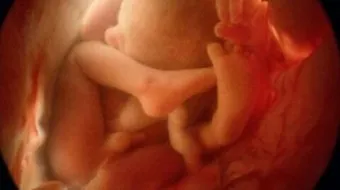

تبدأ الأمّ بالشعورِ بحركة جنينها في الفترة ما بين الأسبوعين السادس عشر والعشرين، أي في نهاية الشهر الرابع إلى الخامس، ويتحرك الجنين بمعدل خمسين حركة في الساعة الواحدة، وأثبت العلماء أن الحركة التي تشعر بها الأم لا تشكل نسبةً من جميع الحركات التي يقوم بها الجنين خلال نومه واستيقاظه وممارسة نشاطاته.